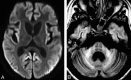

"Hot cross bun" sign in variant Creutzfeldt-Jakob disease